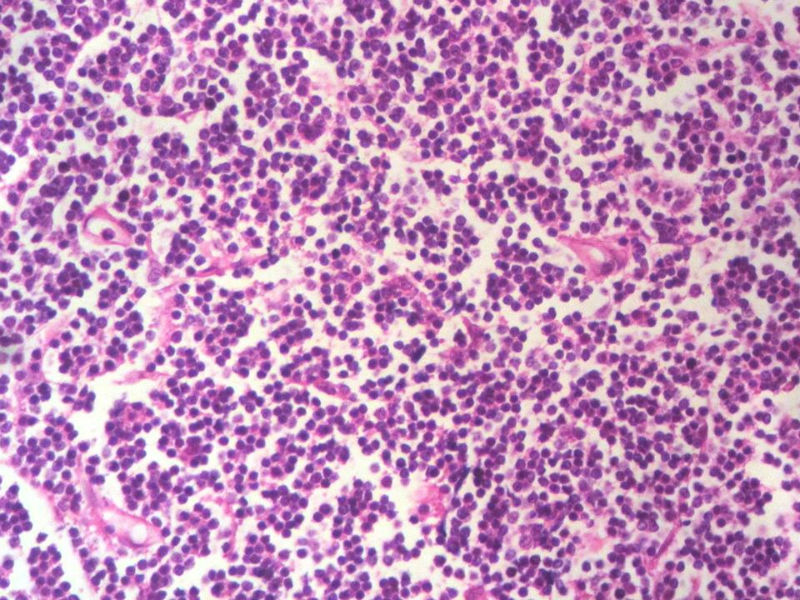

男,49岁,左眼睑球结膜下肿物2个月,手术切除。检查肿块3X2X2厘米,切面灰红色,质软。

本例是发生在特殊部位“结膜下”,HE肿瘤细胞形态形态一致,形似单核样B细胞。B细胞标记若明确阳性,诊断MALT是挺合理的。

HE:  1.MALT粘膜相关淋巴瘤:本例部位很特殊,位于“结膜下”,考虑MALT很合理;但本例镜下细胞形态很一致,诊断MALT是有难度的。

2. SLL小细胞淋巴瘤:就细胞形态而言,有相似之处,考虑SLL也有道理;但如果在没有发现淋巴结,肝,脾,骨髓或外周血具有病变的前题下,原发于结膜的SLL可能是少见的。

3.套细胞淋巴瘤:细胞大小及一致性比较符合;但本例核太规则了,套细胞淋巴瘤很难有这么规则的圆形或椭圆形。

淋巴瘤  细胞小  形态单一  主要考虑小B细胞淋巴瘤

淋巴样细胞。细胞形态单一,细胞小。主要鉴别:

1)粘膜相关淋巴组织淋巴瘤

2)小细胞性淋巴瘤/慢性淋巴细胞性白血病

3)套细胞淋巴瘤

形态结构与细胞大小,似不支持滤泡性淋巴瘤。